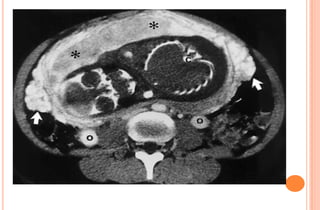

PHOTOS OF CT EVALUATION OF

PREGNANT WOMAN WITH TRAUMA– CT

SCANS DONE AS A PART OF INVESTIGATIONS

DONE IN EMERGENCY --- MATERNAL HEAD

AND ABDOMEN AS PER NEED OF INDIVIDUAL

CASE ---WITHOUT FEAR OF X RAYS

EXPOSURE TO FETUS IN UTERO